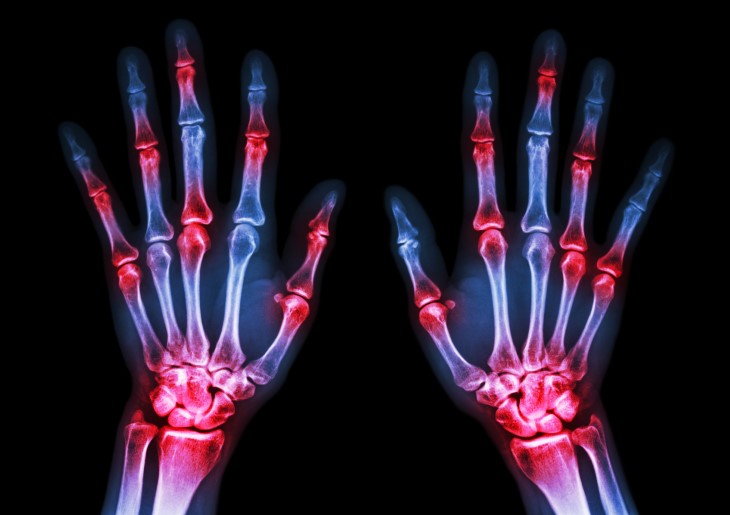

Patients newly diagnosed with rheumatoid arthritis typically focus on managing joint pain, morning stiffness, and selecting appropriate treatment. However, a significant American study has uncovered a hidden threat: as early as the first year of the disease, one in ten patients may be walking around with undetected lung disease that could pose serious health risks.

The study tracked patients in the early stages of rheumatoid arthritis—within two years of diagnosis—and discovered a surprising finding: already at the beginning of their journey, 11% showed signs of interstitial lung disease (ILD) on specialized CT scans (HRCT), even though the condition wasn't necessarily causing noticeable symptoms yet.

Rheumatoid arthritis is the most common inflammatory joint disease and represents an autoimmune condition in which the immune system mistakenly attacks the body. According to Professor Koyti, the disease affects approximately 0.5% of the population, primarily women, with an estimated 50,000 patients in Israel. The disease primarily damages joint cartilage—especially in the hands—causing swelling, inflammation, and without timely treatment, can lead to joint destruction, severe deformities, and disability.